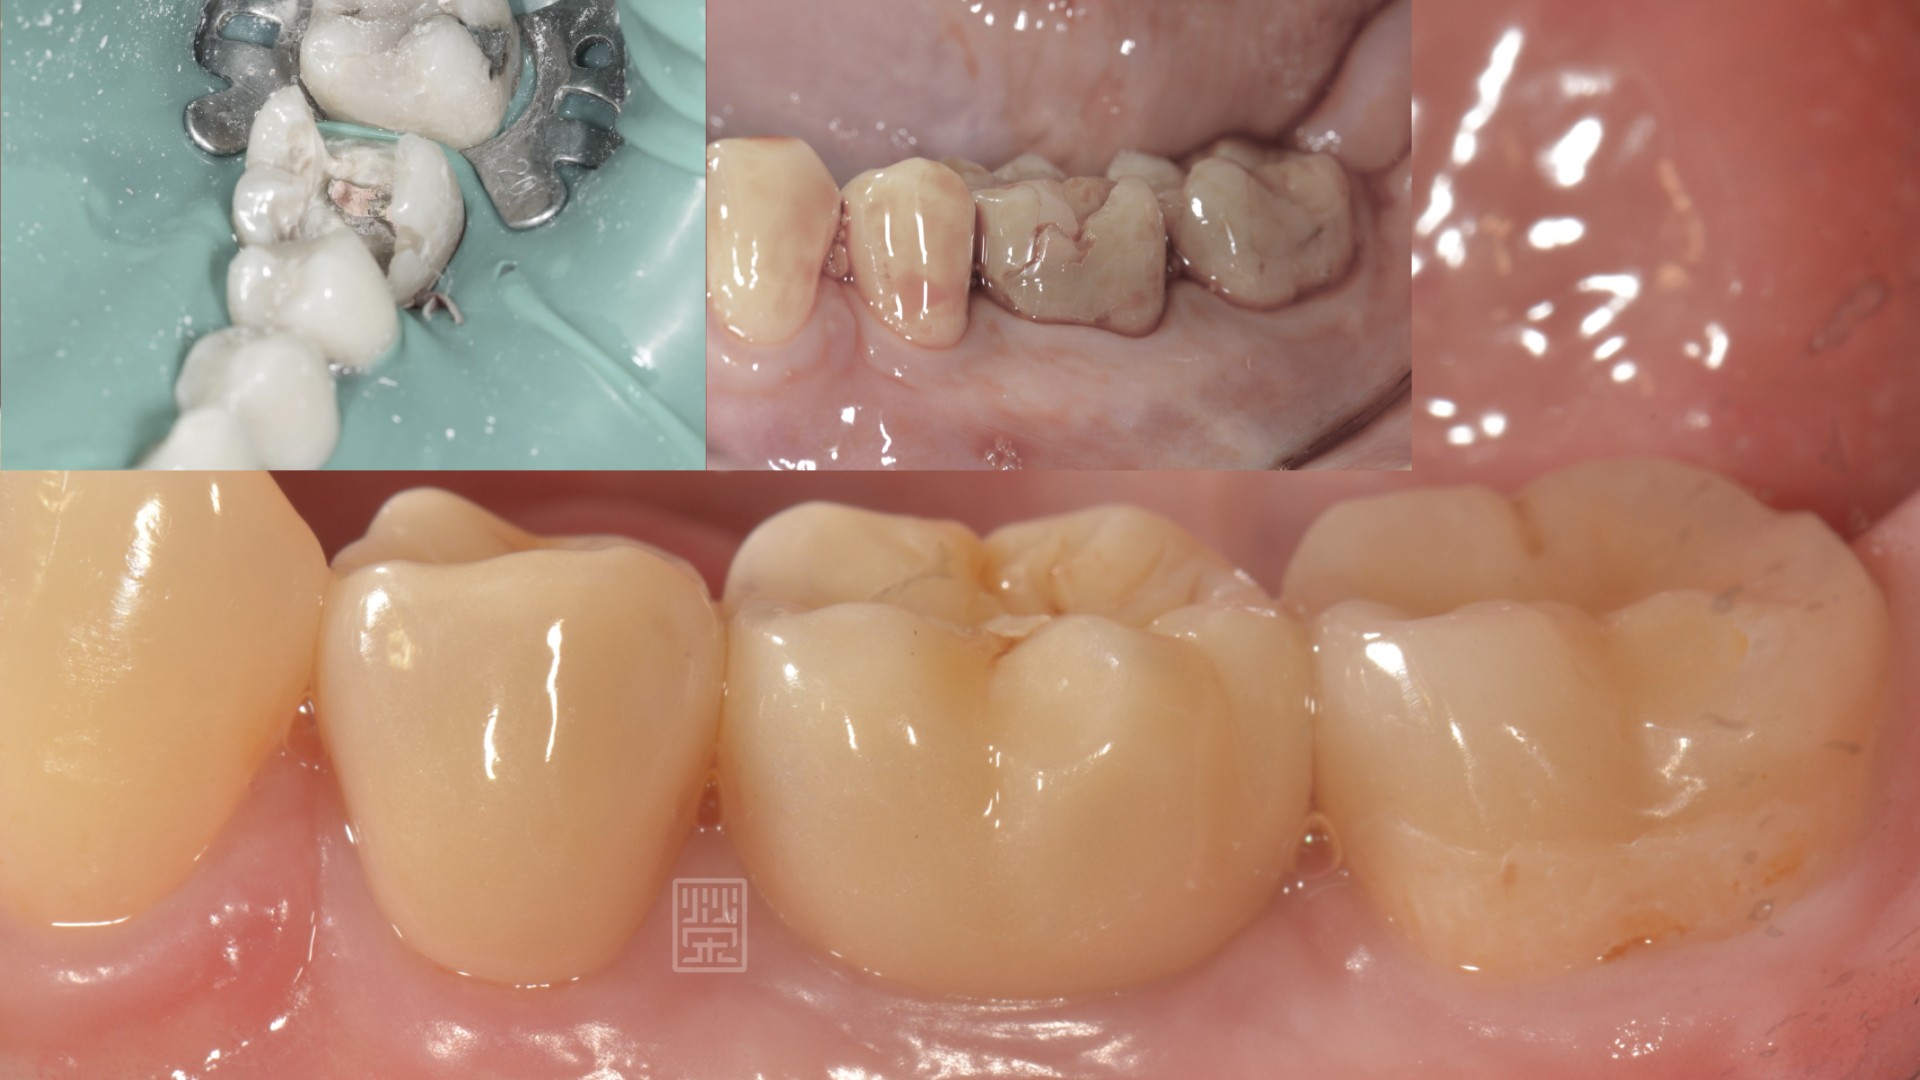

大笑後的尷尬---黑色銀粉填補

首先了解每位病友心中對美的要求,量身打造專屬牙齒美白治療方式,藉由牙周、根管、矯正、植牙、冷光美白、貼片、全瓷冠與顯微鏡微創治療,達到不只健康,更希望讓您發出打從心底燦爛自信的笑容。